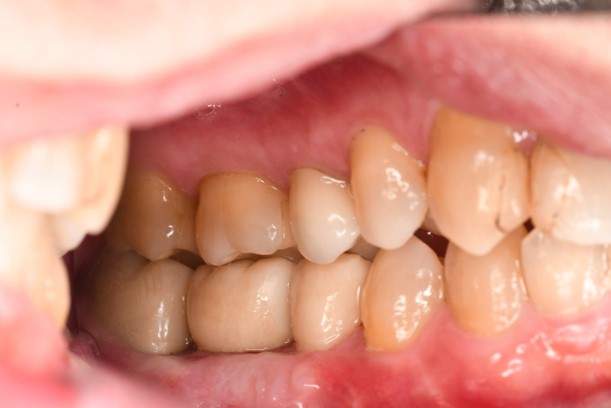

口腔内写真

- Befor

- After

| 年齢 | 50代・男性 |

|---|---|

| 主訴 | 部位:左下6番7番 主訴:左下奥歯腫れて痛い。 |

| 治療内容 | 左下6番抜歯、左下6番7番骨造成、インプラント埋入 |

| 治療費 | 合計:1,232,000円 ・内訳 診断料:55,000円 サージカルガイド2本:66,000円 GBR:110,000円×2本 埋入料:165,000円×2本 静脈内鎮静麻酔:77,000円 2次OPE:22,000円×2本 仮歯:55,000円×2本 上部構造(フルジルコニア):165,000円×2本 (2023年1月現在) |

| 治療期間 | 約8ヶ月 |

| リスク・副作用 | リスク・副作用 |

| 治療方針 | 元々支台歯に負荷がかかりやすいとされている延長ブリッジを抜歯し、1本単体でしっかりかめるようにインプラントを2本埋入した。骨吸収も進んでいたため、※GBR法で骨造成を同時に行った。 治療と並行して、全顎的な歯周病治療も行い、今後は歯周病が進行しないよう、こまめにメンテナンスに通っていただく。 |

| 特記事項 | ※1 GBR・・・骨再生誘導法。骨の高さや厚みを人工骨や人工膜などを使用し再生する方法 |

| 担当者所見 | 6番は歯根分割された被せ物が7番の欠損部との延長ブリッジとされており、強い咬合と歯周病も相まって負荷がかかり動揺し、歯として機能しなくなったため、抜歯となった。 |